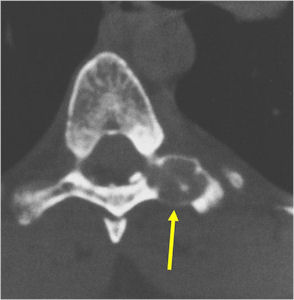

CT Scan:

- More useful for detecting mineralization and evaluating extent of bone destruction than plain X-ray